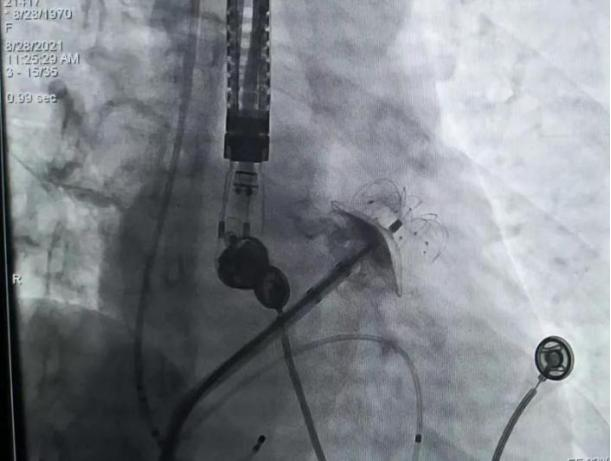

2021年8月28日上午10点,手术正式开始。食管彩超显示左心耳无血栓,李耀东教授带领奎屯医院心内科王飞、杨鸿英、张娟医生进行房间隔穿刺,左心耳造影结果显示为鸡翅型左心耳,在测量左心耳开口宽度和深度后,确定锚定区与封堵区,李教授选择了LAmbre™ 2430封堵器,经输送鞘管送至左心耳实现封堵。造影及食道超声显示均无残余分流,牵拉测试稳定,符合COST原则,释放后取得了理想的封堵效果。随后李耀东教授带领团队对患者4条肺静脉进行冷冻消融,手术历时2小时顺利成功,术后第二日患者活动正常,身体恢复良好。